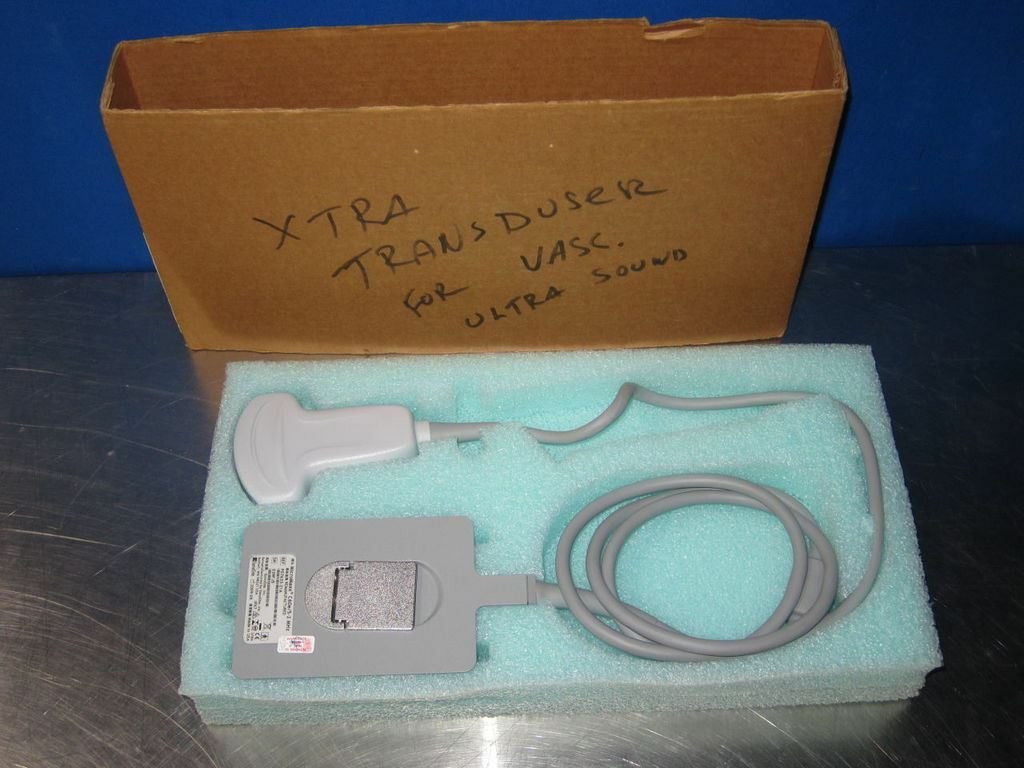

DIAGNOSTIC ULTRASOUND MACHINES FOR SALE

SONOSITE MicroMaxx Probe convex Transducer C60E

Sale price$ 1,638.36